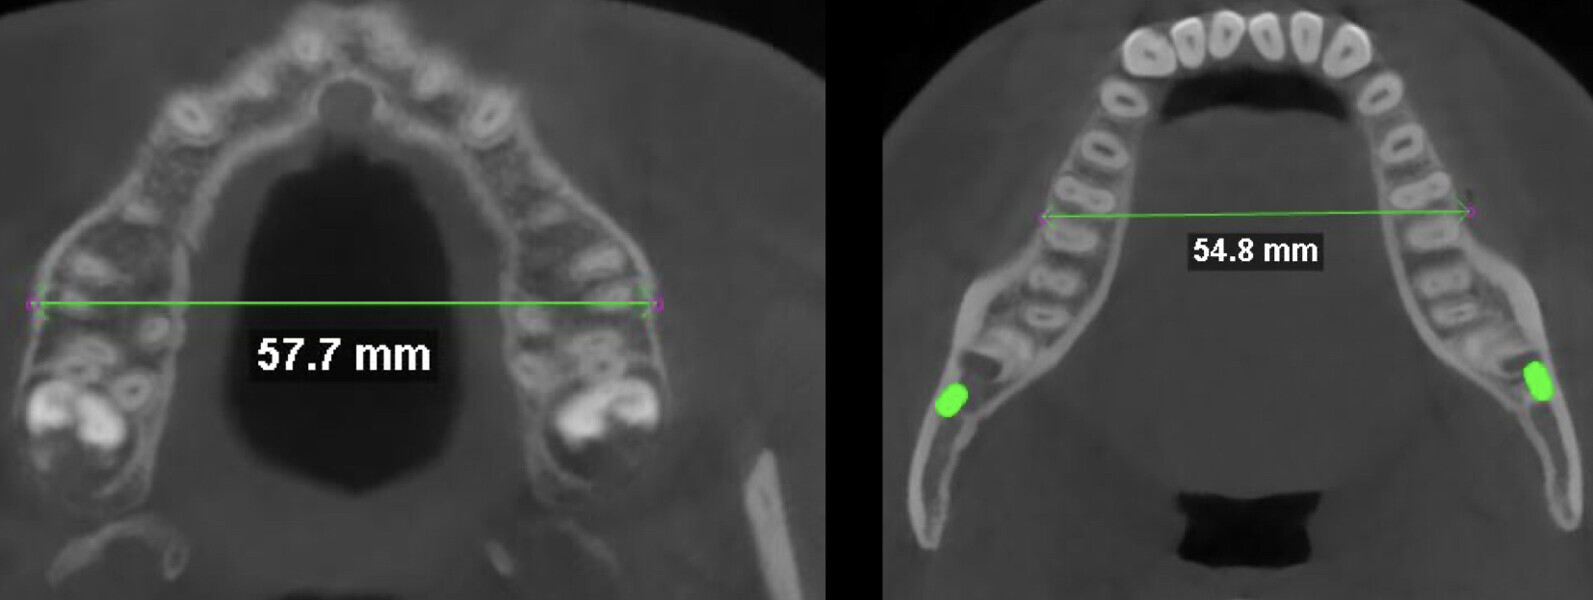

Basal width measurements on the CBCT scan, using the Penn transverse analysis, revealed a maxillary width of 57.7 mm and a mandibular width of 54.8 mm, yielding a +2.9 mm differential. This indicated that skeletal expansion was not necessary in this case (Fig. 5).